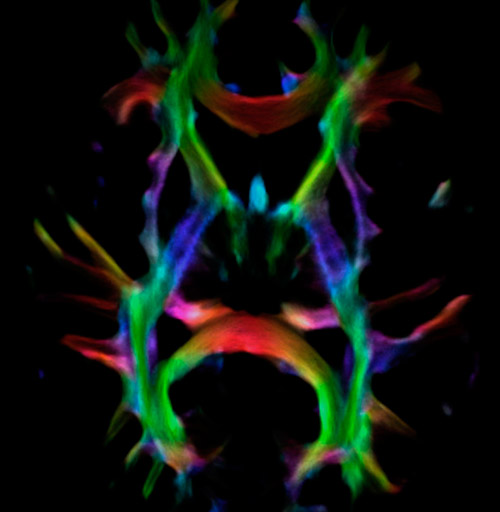

All images were created from the same acquisition in a child using Ingenia 3.0T CX and 32-channel dS Head coil. Diffusion data was acquired at b-values 0, 500, 1000, 2000, 3000. The use of high b-values (3000 s/mm2) effectively suppresses extra-axonal water signal and provides high angular resolution.

CSD of multishell DWI results in the white matter FOD at each voxel. Unlike the conventional diffusion tensor model, this approach enables accurate modeling of multiple fiber populations within a single voxel.

Crossing fibers of the corpus callosum bordered by the superior longitudinal fasciculus as well as within in the pons.